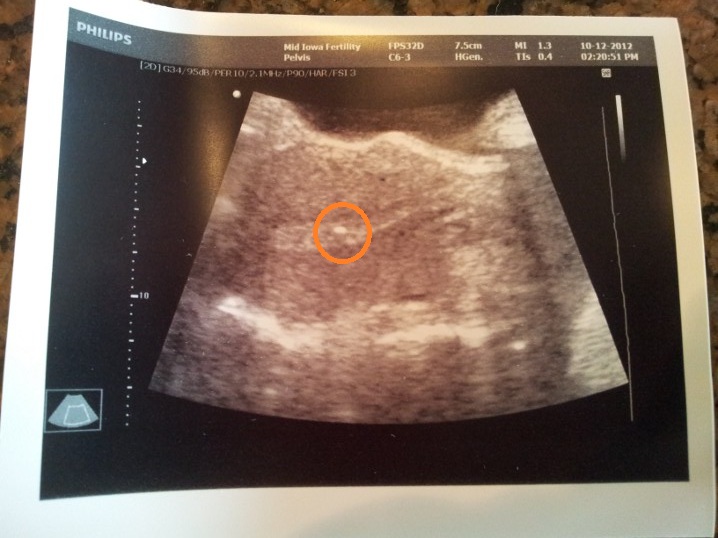

Here’s a photo of the embryos in my uterus. They placed them right next to each other (they pick the specific spot at an earlier appointment during the mock transfer, so they worked to get #2 right next to #1 since they didn’t go in together). The bright spot in the middle of the orange circle is the embryos huddled together:

Good looking blasts!! Lining looks excellent as well. I have a really good feeling about this 🙂

Funny that you can see the lining in that ultrasound. We get so smart, don’t we, when we do IVF? HA!